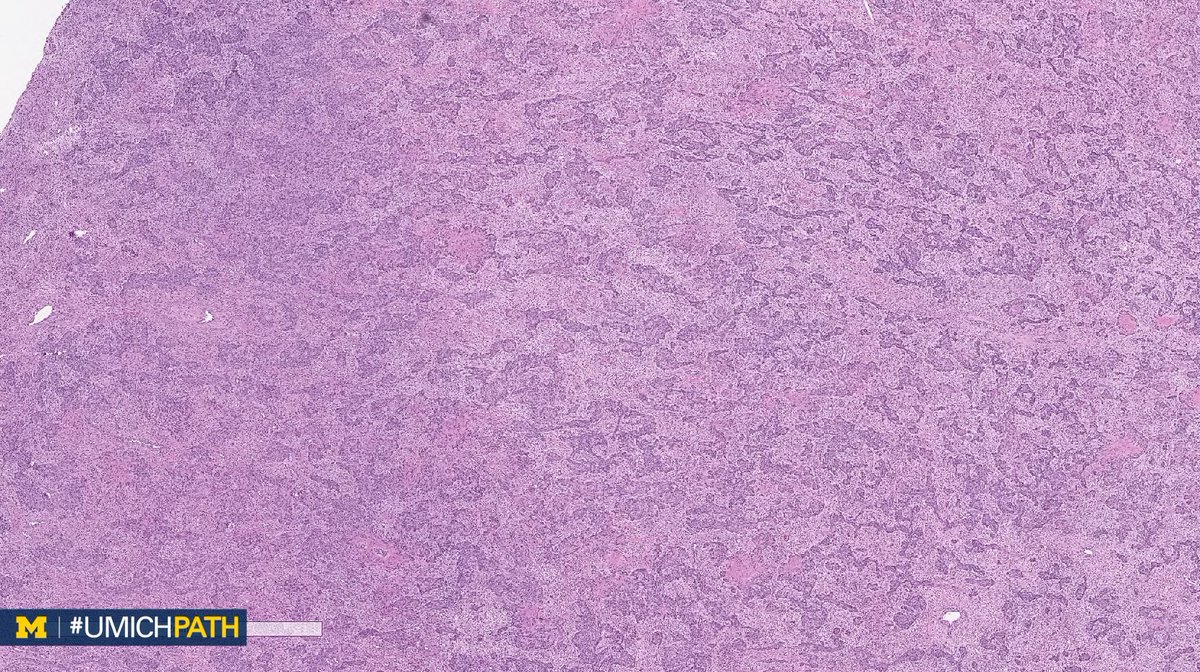

A: (Müllerian) adenosarcoma. Malignant stroma w/ associated benign epithelium (endometrioid or metaplastic); has “Phyllodes-like” architecture w/ stromal condensation. Can be low grade or have sarcomatous overgrowth (>25%) w/ high grade or heterologous sarcoma. #GYNPath #DailyDx